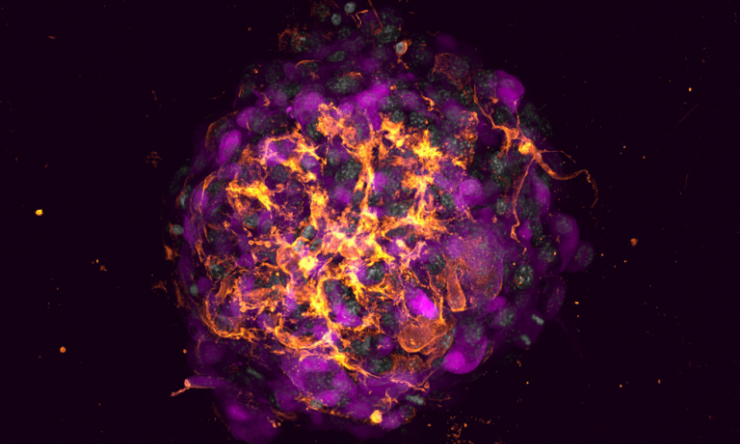

- The image is a human breast cancer organoid in a collagen-based 3D matrix. The image was captured on the Zeiss LSM 880 with Airyscan FAST Confocal Microscope in the Optical Imaging and Vital Microscopy Core at Baylor.

Credit